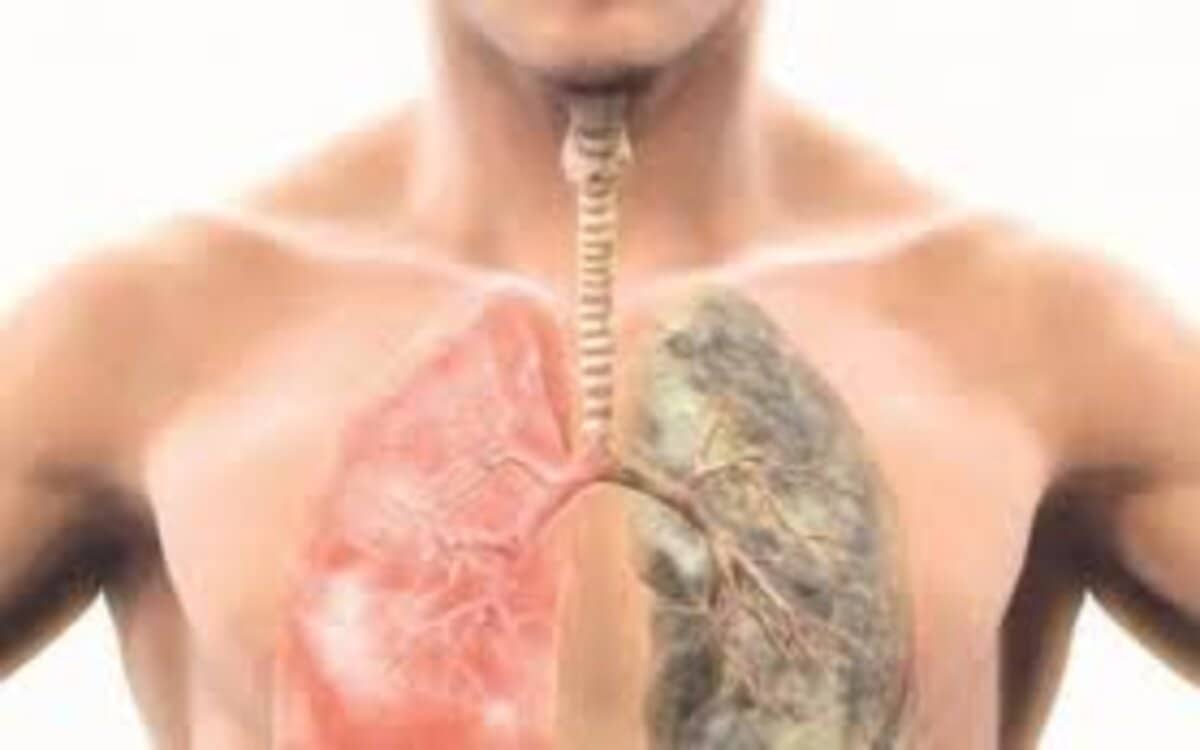

وتروي سيدة أخرى إن بداية تجربتها مع فتق الحجاب الحاجز كان بشعورها بصعوبة شديدة في التنفس وإحساس دائم بحرقان في المعدة وخاصة بعد كل وجبة، وعندما ذهبت إلى الطبيب طلب منها إجراء بعض الفحوصات والتحاليل والأشعة السينية والموجات الصوتية، وأظهرت ضرورة إجراء عملية جراحية لأنها تعاني من فتق في الحجاب الحاجز.

- التدخين بانتظام.

- صعوبة شديدة في التنفس.